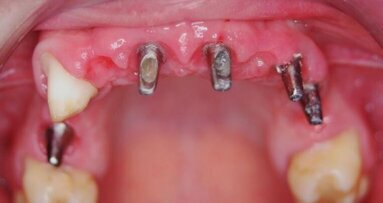

67-letnia pacjentka zgłosiła się do gabinetu stomatologicznego w celu konsultacji w sprawie leczenia implantologicznego. W wywiadzie zgłaszała pewne ...